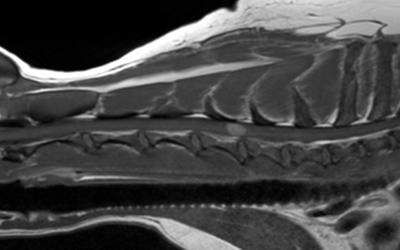

Tom Harcourt-Brown  Patient demographics and behavioural risk factors in canine episodic movement disorders

Episodic movement disorders in dogs are being described with increasing frequency. Some breed-specific forms have been associated with genetic mutations or have specific triggers (such as emotional arousal), but most are idiopathic and have not been associated with a trigger. Stress has been strongly implicated as a trigger in similar human conditions, and our clinical experience supports this in dogs; meaning behavioural therapy might be very useful in managing this lifelong condition.